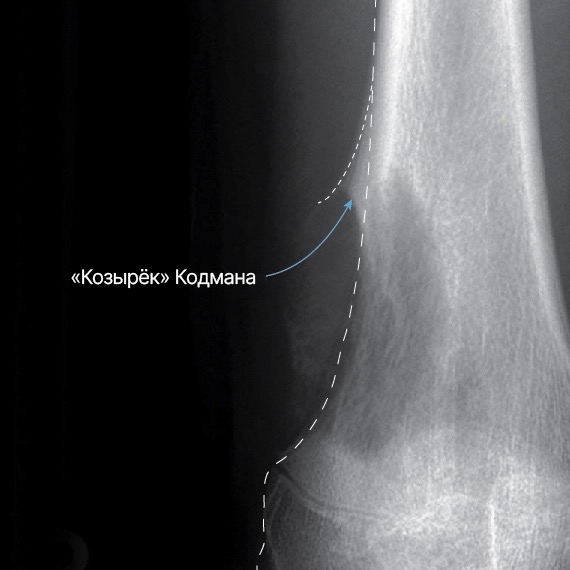

Рентгенография костей — может выявить специфические признаки остеосаркомы, например отслойку надкостницы в виде треугольника — «козырек» Кодмана.

Так на рентгене выглядит козырек Кодмана — отслойка надкостницы при остеосаркоме